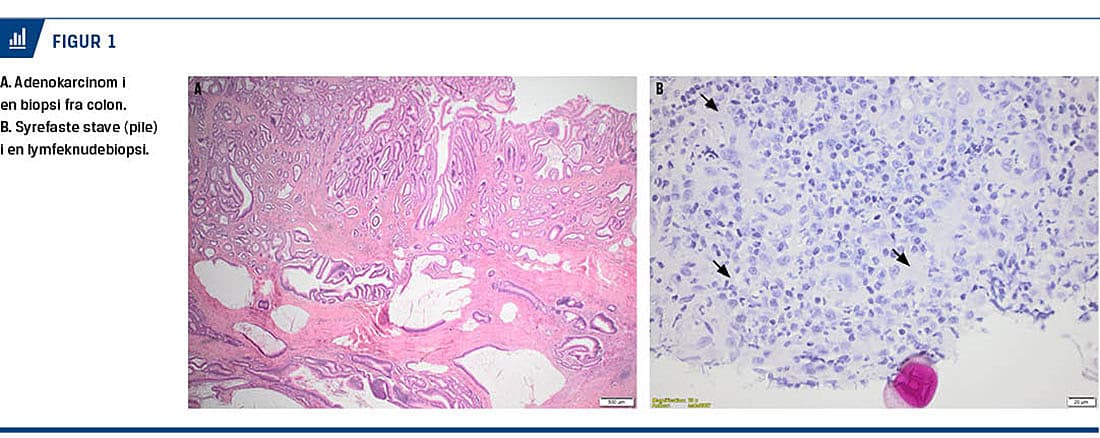

nu dilaterede tyndtarme og en større tumor i sigmoideum, hvilket var foreneligt med et tuberkulom og ileus. Ved sigmoideoskopi fandtes en malignitetssuspekt tumor, og biopsier viste overraskende adenokarcinom (Figur 1A).

Han blev herefter overflyttet til en gastrokirurgisk afdeling, hvor der ved en eksplorativ laparotomi blev foretaget aflastende stomi og taget biopsi fra stenosen omkring coecum. Tumoren blev ikke fjernet, da der fortsat var mistanke om dissemineret sygdom pga. malignsuspekte lymfeknuder i mesenteriet og de multiple tyndtarmsstenoser. Histologisk fandtes der ikke tegn på spredning af adenokarcinomet, men syrefaste stave i lymfeknuden (Figur 1B).